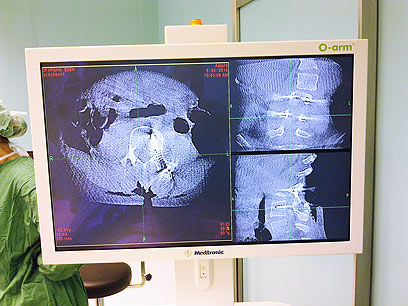

ה- O-arm היא מערכת שיקוף רובוטית מהפכנית, המאפשרת ליצור תמונה תלת ממדית שמציגה למנתח סריקה של 360 מעלות כבר במהלך הניתוח. המערכת מאפשרת למנתח לאמת את השינויים הכירורגיים עוד במהלך הניתוח, לעקוב אחר הניתוח בזמן אמת וכתוצאה מכך מאפשרת דיוק רב יותר ומפחיתה את שיעור הניתוחים החוזרים.

הדמיית מכשיר ה-O-arm בזמן אמת בניתוח.

"מכשיר ה- O-arm מאפשר לקבל הדמיה תלת מימדית בזמן הניתוח, לגלות בזמן אמת אם היו אי דיוקים בהכנסת שתלים ולבצע את התיקונים במקום. אני צופה שהשימוש בטכנולוגיה המהפכנית הזו יוריד את מספר הניתוחים החוזרים באופן משמעותי, יפחית את הקרינה אליה נחשף המטופל ויגביר את מידת הדיוק של הניתוח".